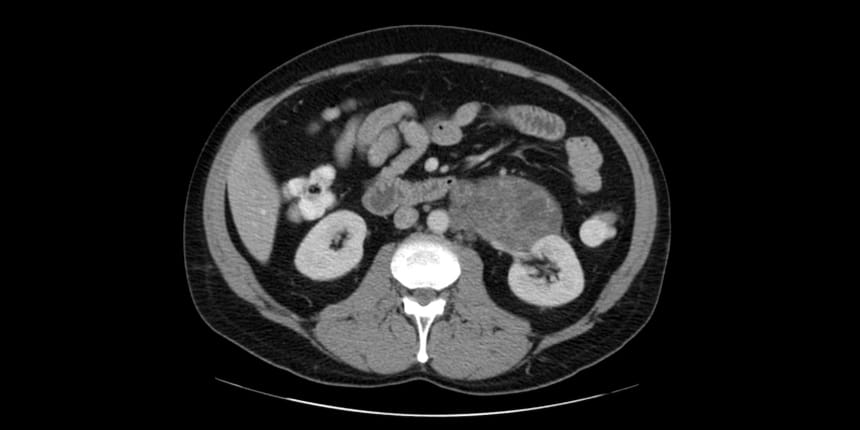

This test uses a rotating X-ray beam to create a series of pictures of the body from many angles. A computer processes the information provided by the scan and produces a detailed cross-sectional image of the selected part of the body. To highlight details on a CT scan, a dye may be injected into a vein. The CT scan is especially valuable in identifying the spread of tumors to the lymph nodes and other parts of the body.